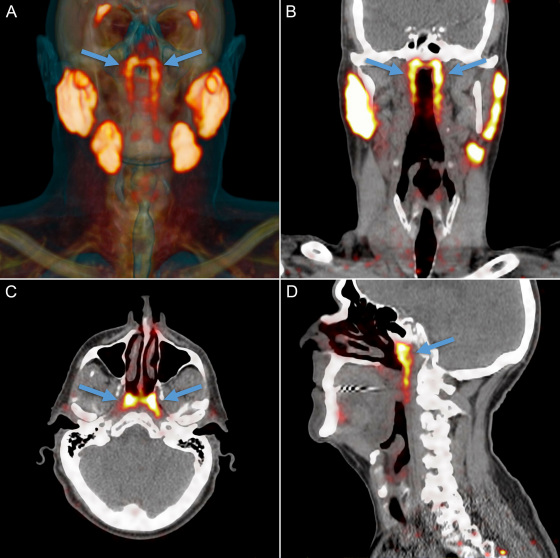

研究小组起初是通过放射性示踪剂来研究前列腺癌的 , 这种放射性示踪剂在进入人体以后会与前列腺癌细胞中的蛋白质PSMA (前列腺特异性膜抗原)结合 , 这其实就是癌细胞被标记的过程 。

然后通过扫描追踪放射性示踪剂我们就能知道癌细胞的位置 , 这种利用示踪剂成像诊断法被称为“PSMA PET-CT” 。

不过PSMA这种蛋白质不仅存在于前列腺癌细胞中 , 在人体的唾液腺阻止中也存在 , 因此在扫描成像的过程中就标记出了人体中所有唾液腺的位置 。

也正是通过以上的方法 ,研究小组意外的发现了新的唾液腺 , 并且把这种新发现的器官命名为“Tubarial Glands (管状腺)”